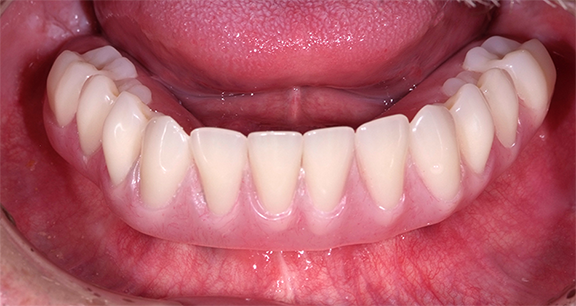

Implant-Retained and Implant-Supported Removable Prostheses

An implant-retained and implant-supported removable prosthesis may be fabricated by using a bar or a conical, titanium abutment with a 5-degree taper (Figure 18).49 In the next case, a fixture-level impression was made and records were registered and sent to the laboratory with the abutments (preselected based on the height of the mucosal cuff) for framework and prosthesis fabrication.49 The prosthesis had recesses on its intaglio surface to permit pickup of the abutment caps (Figure 19).49 The abutments were attached to the implants in the mouth (Figure 20). A jig/index provided by the laboratory (Figure 21) was used to seat the abutments intraorally so that they were positioned exactly as they were on the master cast. Gold caps were placed over the abutments and were picked up in the prosthesis intraorally (Figure 22).49 (Gold caps that fit over the abutments provide excellent retention, which improves over time.)50 The prosthesis was adjusted, finished, polished, and placed in the mouth (Figure 23). The prosthesis was entirely supported by the implant abutments.49 It had excellent retention and stability (almost like a fixed restoration) because it was entirely implant-supported; yet, it was removable.49

Fig 23. The prosthesis was placed in the patient’s mouth.